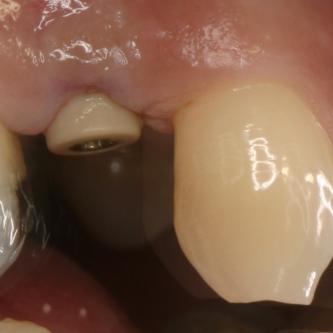

Exemple 1: Ce patient a perdu son incisive centrale gauche lors d'un accident. Un implant a été posé

Exemple 1: L'implant remplace la racine de la dent manquante

Exemple 1: L'implant s'est intégré dans l'os, une empreinte est effectuée. Le laboratoire peut réaliser la couronne en céramique.

Exemple 1: résultat final.